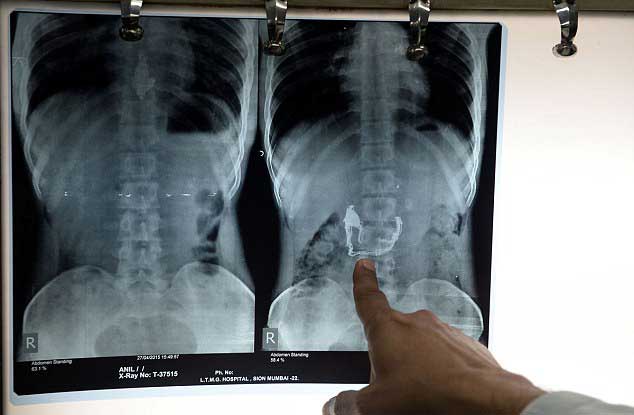

X-ray of the suspect s stomach where the missing jewellery can be seen

The man denied snatching the chain from a woman in the street in Mumbai and swallowed it in a desperate bid to conceal his crime last week, but hospital X-rays suggested otherwise.